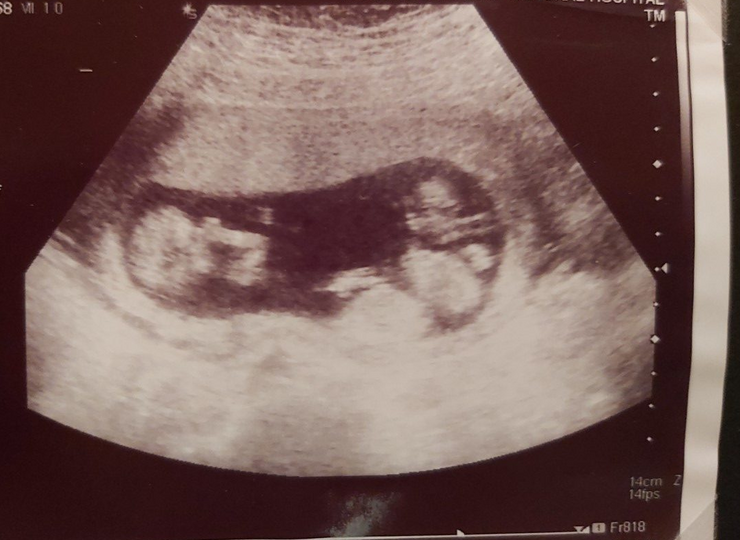

Danny shares the story of losing one of his triplets to Necrotizing Enterocolitis (NEC)